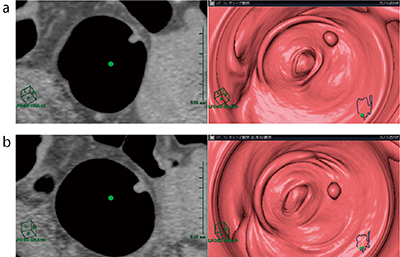

時々,前処置が悪く,タギングされたCT値の高い残渣が散在していることがあるが,キーボードのボタン1つでカラーマップを変更でき,タギングされた残渣かそうではないかの判断に役立つ(図4)。

図4 通常のカラーマップ(a)と,CT値150HU以上を

白く表示させたカラーマップ(b)